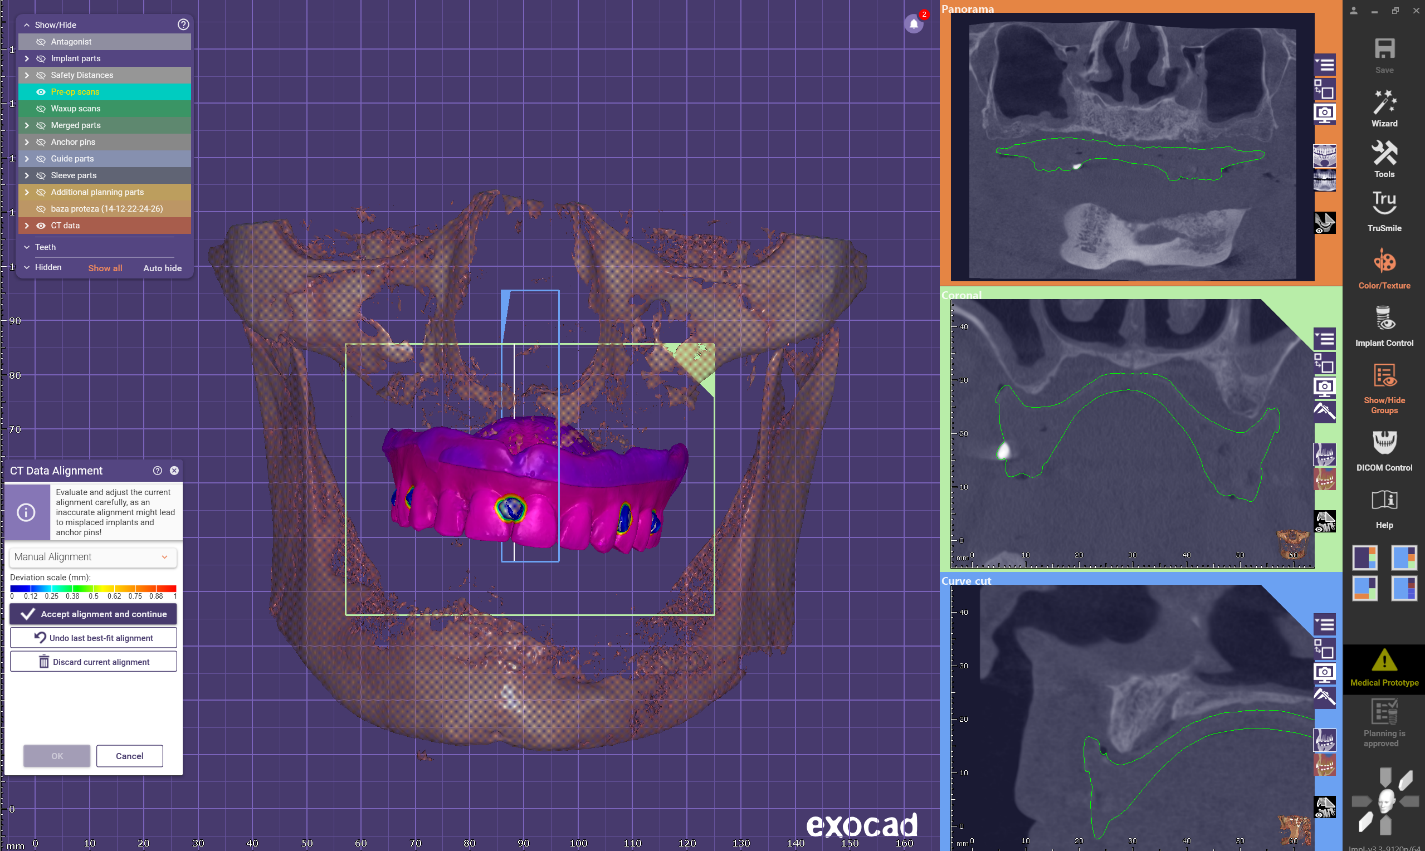

A new waxup was generated in Exocad and printed as a try in to check occlusion but also esthetics at some degree and have a proprosthetic implant positioning available in the planning step.

Implant placement planning done in EXOPLAN involved careful digital matching of the CBCT, wax-up, and facial scan data, resulting in an accurate, digitally-produced try-in prosthesis (Fig. 8). The validated prosthetic design was subsequently integrated with the software to plan placement of five strategically positioned implants in the upper arch.

Surgery was performed and after suturing scans of the patient where only performed for the upper arch and this scans where merged to the preoperator projects.

The scanned arch and implant position will be used to modify the waxup intaglio and cut out screw channels and direct to MUA connections.